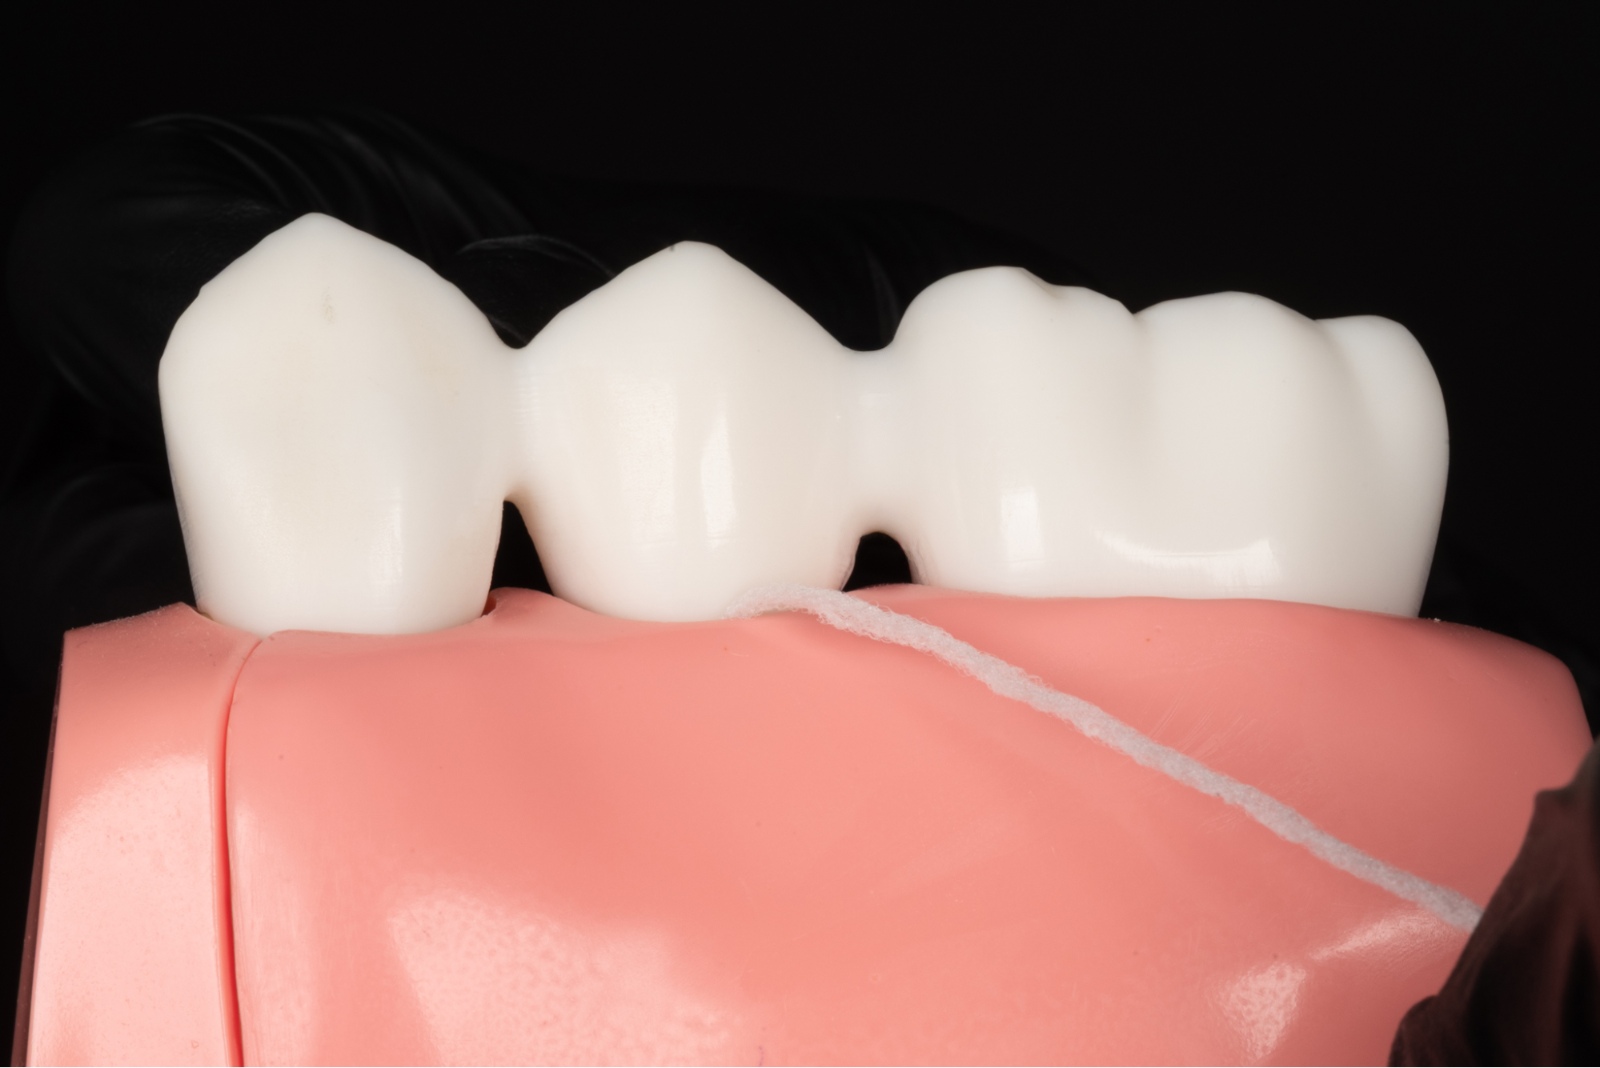

Pacjenci, którzy rozważają uzupełnienie braków w uzębieniu, często wahają się między implantem zęba a rozwiązaniami takimi jak mosty protetyczne czy protezy ruchome. Warto jednak wiedzieć, że w porównaniu z nowoczesnym leczeniem implantologicznym, zarówno most protetyczny, jak i tradycyjne protezy są rozwiązaniami kompromisowymi.

Aby uzupełnić jeden brakujący ząb za pomocą mostu protetycznego, najczęściej trzeba wykonać konstrukcję trójpunktową. Całkowity koszt takiego rozwiązania jest zbliżony do ceny implantu zęba z koroną, jednak implanty zębowe pozwalają zachować integralność sąsiednich zębów.

Oszczędność tkanek – brak ingerencji w zdrowe zęby

Założenie mostu protetycznego wymaga oszlifowania sąsiednich, często zupełnie zdrowych zębów, które stają się filarami konstrukcji. Wszczepienie implantu pozwala tego uniknąć -to uzupełnienie braków bez ingerencji w strukturę sąsiednich zębów.

Higiena i trwałość

Pojedynczy implant zęba z koroną funkcjonuje jak naturalny ząb i jest łatwy w oczyszczaniu. Most protetyczny, jako konstrukcja zespolona, utrudnia higienę, co może prowadzić do stanów zapalnych dziąseł i skrócenia jego żywotności.